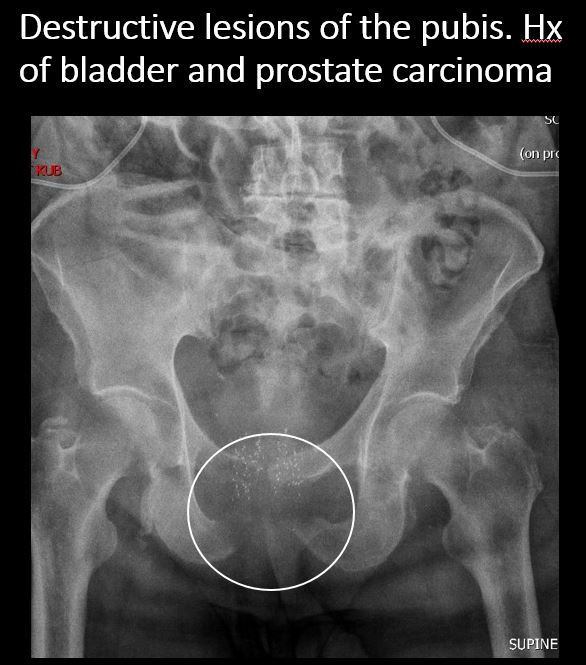

There is a lytic, blastic, or destructive lesion of the spine, pelvis, femurs, or ribs. |

No | NA |